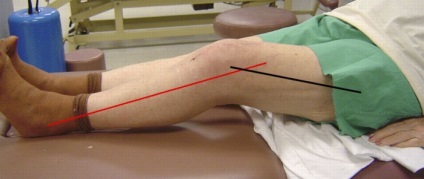

contractura

Ea apare rar (0,1%), deoarece implantarea de proteze folosind individuale în funcție de vârstă, sex și caracteristici anatomice, dar există precedente. Umflarea în zona câmpului chirurgical, încălcarea funcției de suport, dureri articulare - simptome ale bolii. Ignorarea simptomelor duce la o scurtare a șchiopătatul piciorului.

picior uman este într-o stare relaxată, dar nu poate sta în picioare drept. Se pare că nu a existat nici o reabilitare post-operatorie si proteza nu ar trebui în întregime corectă.

Contractura poate fi temporară sau permanentă. Poate reduce cinematica sau imobilitate totală. Omul caută în mod conștient pentru a reduce disconfortul, astfel încât în perioada postoperatorie este încercarea de a muta piciorul, astfel încât să nu doare. Reabilitarea are nevoie de încărcare regulată a unui anumit caracter. În cazul în care acestea nu sunt fluxul sanguin natural si incetineste vindecarea, patologie duce la cicatrici si mod persistent.